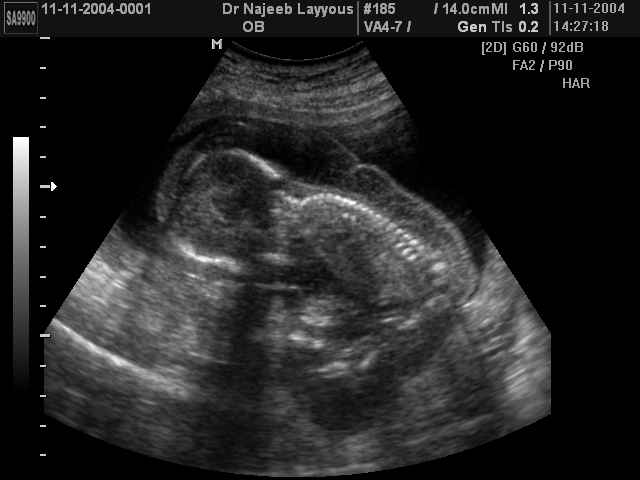

- لقطات فيديو للجنين بجهاز الموجات فوق صوتية رباعي الأبعاد

- صور جانبية لرأس الجنين